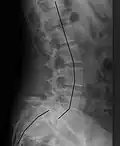

![]() | |

| X-ray of the lateral lumbar spine with a grade III anterolisthesis at the L5-S1 level | |

Spondylolisthesis refers to a condition in which one spinal vertebra slips out of place compared to another.[1] While some medical dictionaries define spondylolisthesis specifically as the forward or anterior displacement of a vertebra over the vertebra inferior to it (or the sacrum),[2][3] it is often defined in medical textbooks as displacement in any direction.[4][5]

Spondylolisthesis is graded based upon the degree of slippage of one vertebral body relative to the subsequent adjacent vertebral body.[6] Spondylolisthesis is classified as one of the six major etiologies: degenerative, traumatic, dysplastic, isthmic, pathologic, or post-surgical.[7] Spondylolisthesis most commonly occurs in the lumbar spine, primarily at the L5-S1 level, with the L5 vertebral body anteriorly translating over the S1 vertebral body.[7]

Classification by degree of the slippage, as measured as percentage of the width of the vertebral body:[17] Grade I spondylolisthesis accounts for approximately 75% of all cases.[7]

- Grade I: 0–25%

- Grade II: 25–50%

- Grade III: 50–75%

- Grade IV: 75–100%

- Grade V: greater than 100%